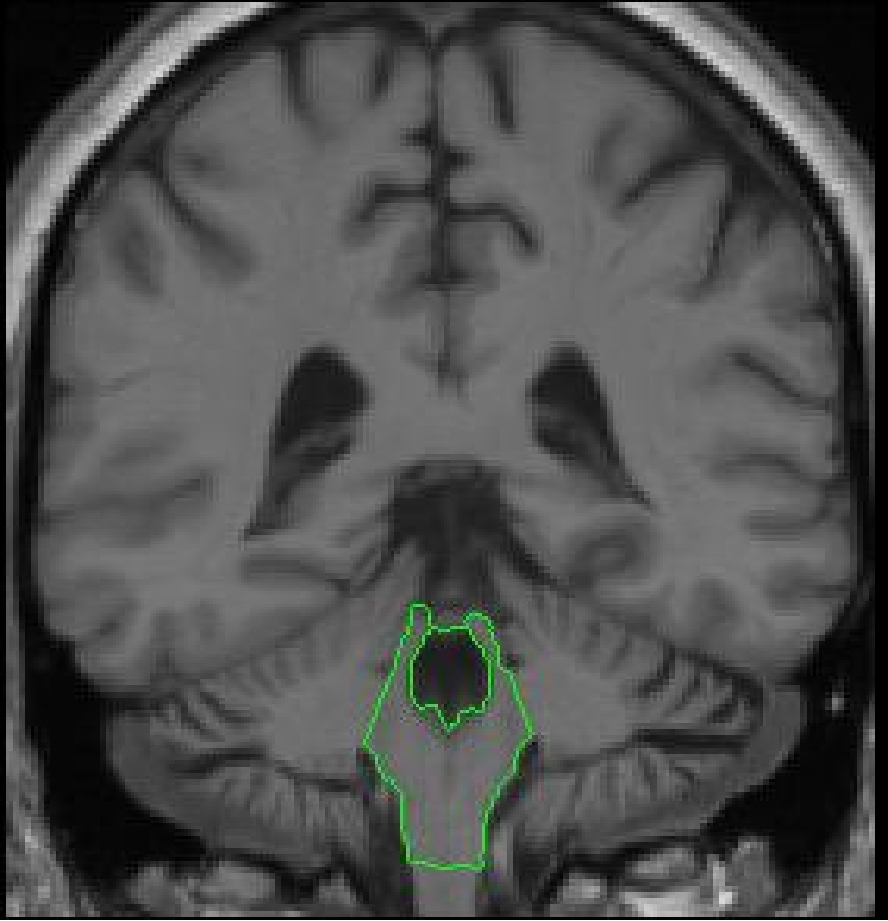

As soon as the superior brainstem line appears, it will be used as the marker

for the division between the VDC and the brainstem. The two structures are

separated by drawing a line which bisects the vertical sulci line (appearing

as a dot), such that everything above it will be labeled VDC and everything

below it brainstem.

Before the appearance of the cerebellum, there is a dramatic change in the

lateral extent of the brainstem. The more anterior of the slices in this region

will contain a uniformly colored structure which is extracted and labeled as

part of the brainstem (there is no cerebellum present at this point). More

posteriorly, one slice before the cerebellum first appears, the lateral extents

of the brainstem are segmented separately to exclude the middle cerebellar

penducles.